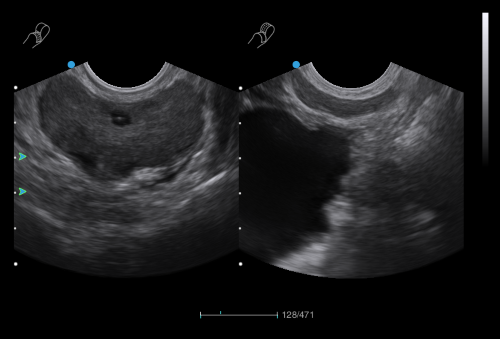

Urology

· In-plane Biopsy Guidance indicates the insertion path and needle tip position during biopsy operation.

· Out-of-plane Biopsy Guidance supports preset of needle size and insertion depth to minimize the risk of potential damage to surrounding tissues.

· Compatible with Bi-plane probe for efficient urology examination.

Bi-plane Dual Micro-convex Probe

Bi-plane Linear and Micro-convex Probe